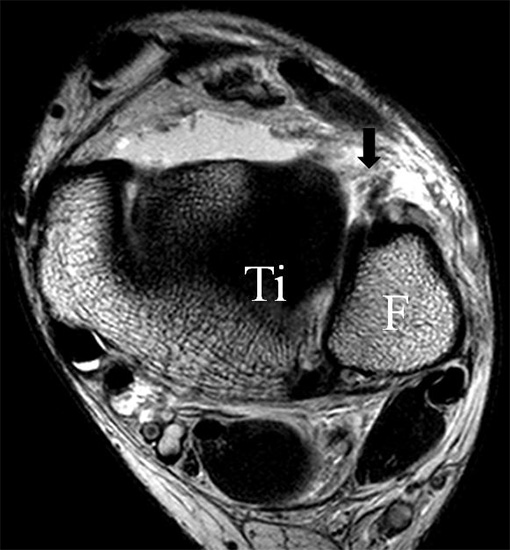

Die Kombination aus 3 Tesla Hochfeldtechnik und/oder Verwendung hochauflösender Spulen (Empfangseinheiten des Signals) erhöht die Signalausbeute. Dies erlaubt mit akzeptablen Messzeiten (3-4 Minuten pro Sequenz) im Routinebetrieb eine Darstellung mit einer Schichtdicke von 1-2 mm und einer Ortsauflösung von 0,2 x 0,2 mm in der Schichtebene in den anatomisch am besten zeichnenden 2D Turbospinechosequenzen. Der Unterschied der diagnostischen Wertigkeit zwischen einer kernspintomographischen „Standarduntersuchung“ und einer HR-MRT wird besonders in der chondralen Diagnostik sichtbar (Abb. 1 a-c). Unter Verwendung von 3D Sequenzen, die jedoch entscheidende Schwächen bei der Darstellung der Ligamente aufweisen, werden sogar Schichtdicken weit im Submillimeterbreich erreicht. Eine weitere Erörterung der Sequenz spezifischen Eigenheiten soll jedoch an dieser Stelle unterbleiben.

PD fs HR axial. Klare Darstellung eines filigranen, knapp über 1 mm breiten LFTA (Pfeil). Fibula (F).

Abbildung 3

Das LFTA verbindet die antero-inferiore Fibulaspitze mit dem Processus lateralis tali und inseriert hier an einem oder zwei kleinen Tuberkeln 3. Der in Neutralposition horizontale Verlauf erleichtert die kernspintomographische Darstellung in dieser Standardebene. Das LFTA weist durchschnittlich eine Breite von knapp über 2 mm auf 4. Somit sind bei einer Routinedarstellung in 3 mm Schichtdicke Anschnittsphänomene, die die Diagnostik erschweren, regelmäßig anzutreffen. Dementsprechend sind auch die ligamentären Subfaszikel nicht zu differenzieren. In koronarer Darstellung ist dies aufgrund der hohen Auflösung in der Schichtebene jedoch möglich (Abb. 2 a-c), wobei hier wiederum eine Integritätsbeurteilung des Bandes erschwert ist. Unter Verwendung hochauflösender Techniken im Millimeterbereich (Schichtdicke) sind hingegen auch in der axialen Ebene die subfaszikulären Strukturen zu beurteilen (Abb. 3).